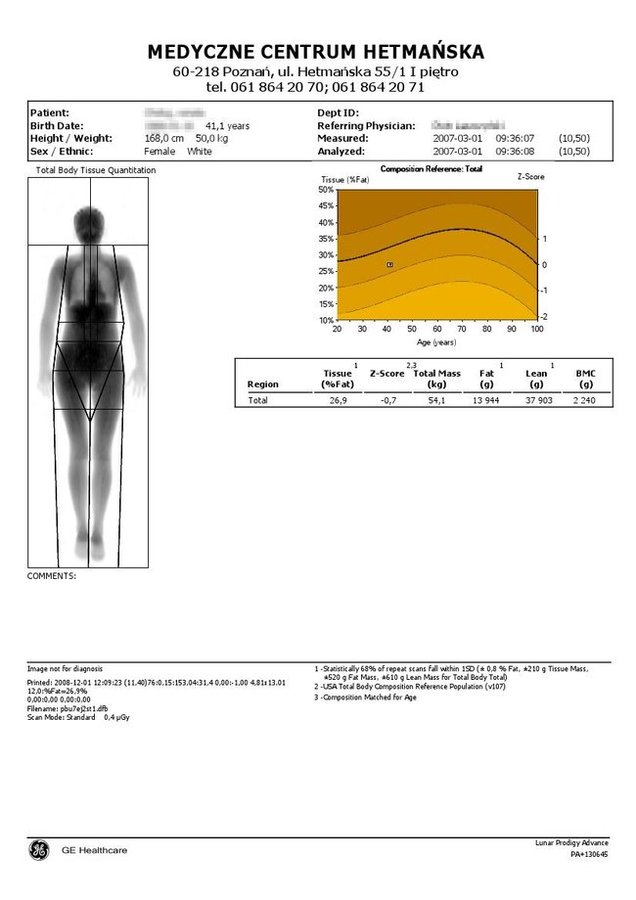

• W badaniu Total Body ocenie poddana zostaje masa tkanki kostnej całego szkieletu poprzez wyznaczenie gęstości w g/cm². Następnie dzięki specjalnemu oprogramowaniu aparat Lunar – Prodigy porównuje wynik do wartości szczytowych dla danej płci lub kontrolnej grupy rówieśniczej.

• Możliwa jest również ocena mineralizacji tkanki kostnej w poszczególnych segmentach szkieletu.

• Podczas badania densytometrycznego całego kośćca analizie poddany zostaje także skład ciała z wyznaczeniem masy tkanki tłuszczowej (Fat mass) oraz jej procentowego udziału względem masy ciała (% Fat), a także rozkładu percentylowego względem populacji referencyjnej.

• Możliwa jest również ocena masy tkanki mięśniowej (wyznaczenie Lean Body Mass).

Ramię densytometru przesuwa się nad pacjentem skanując cały kościec i skład ciała. Na ekranie komputera pojawia się skanowany obraz, dokonywany jest pomiar gęstości mineralnej kości w g/cm2, pomiar zawartości tłuszczu i tkanki mięśniowej w gramach.

Pacjent otrzymuje wynik przeprowadzonego badania w formie wykresu i tabeli.